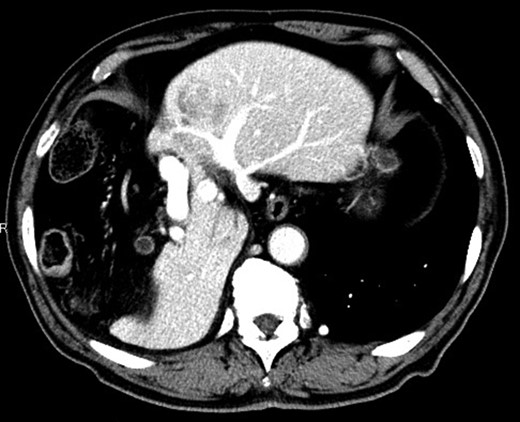

Considering the small remnant right lobe and abnormal ICG15, we planned to perform laparoscopic anatomical S3 segmentectomy. The procedures were performed using a pressure-controlled carbon dioxide pneumoperitoneum, which was maintained below 12 mmHg. Intraoperative findings showed hypoplasia of the right hepatic lobe and hypertrophy of the left hepatic lobe (Fig. 2). Intraoperative ultrasound (IOUS) was performed to confirm the location of the tumor and its relationship to the adjacent structures. The Glissonian pedicle to S3 was isolated with meticulous dissection and was then transected using the SigniaTM Stapling System and Endo GIATM Curved Tip Reload with Tri-StapleTM Technology 30 mm, Vascular Medium (Covidien, USA) (Fig. 3). The ischemic margin of S3 was marked using electrocautery (Fig. 4). Using the crush-clamp method with a harmonic scalpel (Ethicon, USA), the liver parenchyma was transected along the left hepatic vein (Fig. 5). Pringle’s maneuver was performed by clamping the hepatoduodenal ligament using the tourniquet method for 15 min with following a 5-min release period, and a total of fourteen temporary clamps were performed during parenchymal resection. The resected specimens were removed in a retrieval bag through an umbilical port site. The resected specimen showed a 41-mm simple nodular type of HCC and a 5-mm tumor-free resection margin (Fig. 6). Each port was placed as shown in Fig. 7.

The small right hepatic lobe is not fixed to the diaphragm. The arrow (white) shows the lesion in S3.